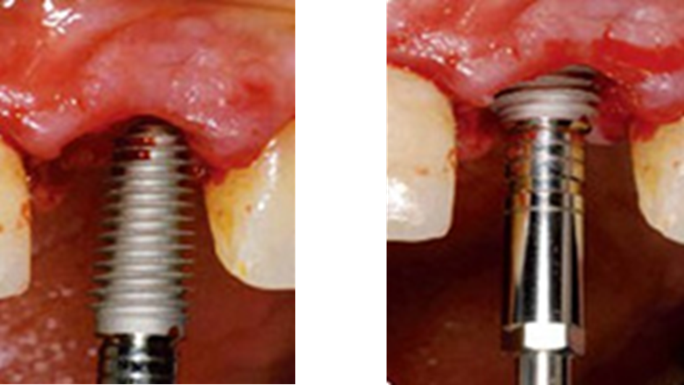

Clinical case: Immediate post-extraction insertion of implant & immediate loading

- Courtesy of Prof. Giuseppe Luongo, Italy -

AnyRidge, immediate loading, single implant, multicenter study, maxillary anterior, Prof. Giuseppe Luongo, single replacement

AnyRidge implant system

Immediate functional loading of single implants: a multicenter study with 4 years of follow-up

/J Dent Res Dent Clin Dent Prospect 2018; 12(1):26-37 | doi: 10.15171/joddd.2018.005

https://www.ncbi.nlm.nih.gov/pubmed/29732018